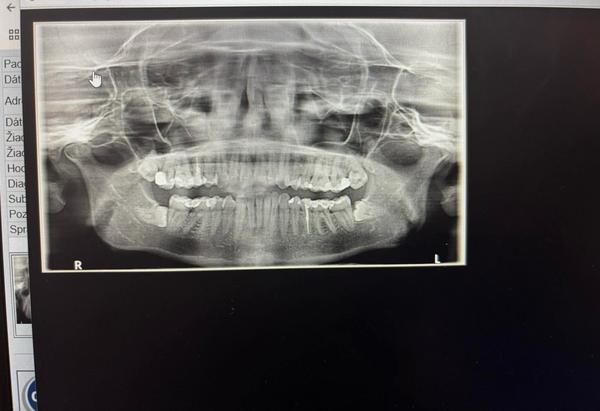

Vidíte na RTG akútne zubné problémy?

Ahojte prosím vás kým sa dostanem k zubárovi viete mi poradiť ? Vidíte niekto na tomto rtg nové kazy ? Je tam niečo akútne na riešenie ? Ďakujem

Nedá sa zväčšiť rtg a ten je na kazy nie práve najlepší lepší je zahryzovy lepšie vidno medzozubne priestory. Ak 8micky nerobia problém ze netlačí neriesit je to zbytočné ak by robili problém tak von. Ak by sa dal zväčšiť bolo by lepšie, treba pridať do komentára

Na diagnostiku kazov slúžia malé záhryzové snímky (bite wingy), nie toto.

@kikus138 ja len vidim,ze si daj vybrat osmicky, mas ich nalezato, lebo ti mozu sposobit velke problemy.

@kikus138 moze ti sposobit problemy s celustnym klbom, mozu sa ti okolo neho vytvorit cysty, moze tlacit na susedne zuby a tym ich poskodit, okolo lezatej osmicky sa ti moze vytvorit infekcia, nasledne opuch, zacervenanie, moze ti sposobit bolest v uchu, dasien.

@kikus138 Nevyznám sa, ale asi spodné osmičky tlačia na vedľajšie zuby.